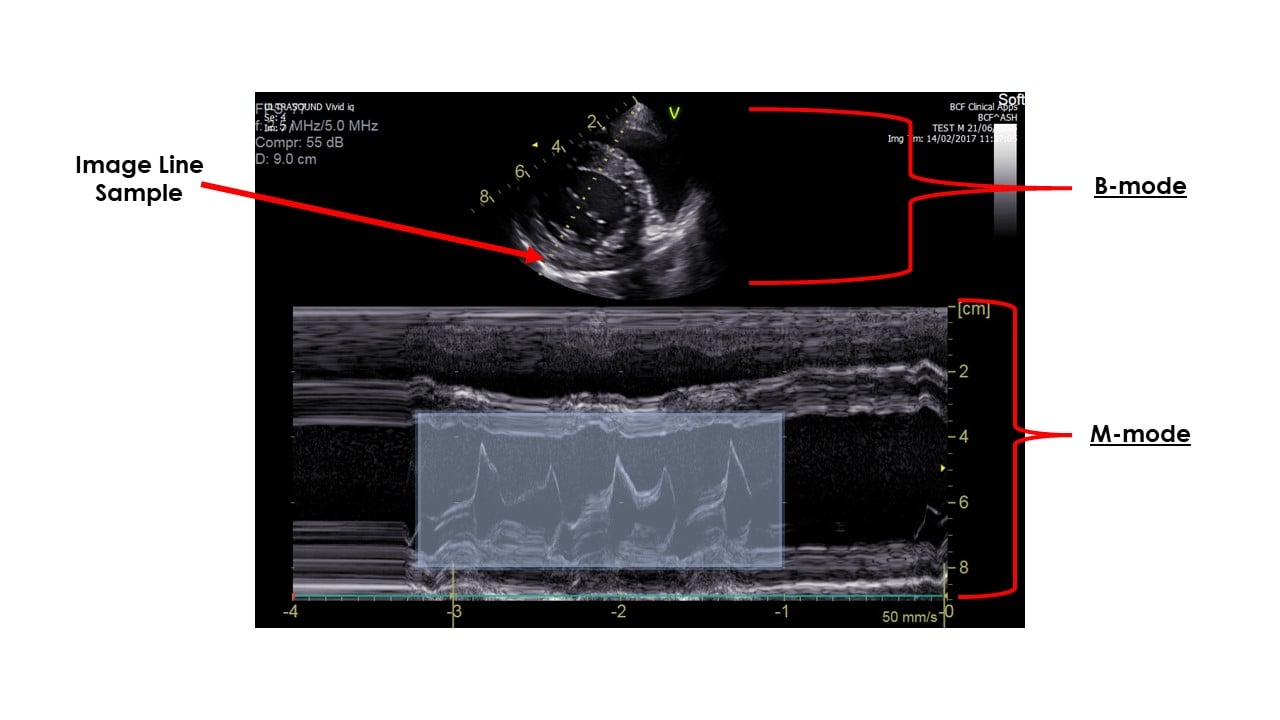

M-Mode (Motion Mode) Doppler Ultrasound, a foundational imaging technique in echocardiography, continues to evolve within the broader ultrasound market landscape. While facing competition from advanced modalities, specific trends are shaping its trajectory heading into 2026.

By 2026, the primary growth driver for M-Mode Doppler is its seamless integration within comprehensive echocardiography systems. M-Mode’s unparalleled temporal resolution remains critical for precise assessment of cardiac chamber dimensions, wall thickness, and valve motion timing (e.g., mitral valve E-point septal separation for LV function, aortic valve opening/closing). Its synergy with 2D imaging (for precise beam placement) and Doppler modalities (Pulsed-Wave, Continuous-Wave, Color Flow) within modern ultrasound platforms ensures its continued indispensability in standard protocols for diagnosing cardiomyopathies, valvular heart disease, and pericardial effusion. Demand will be sustained by clinical necessity in both routine screenings and complex cardiac assessments.